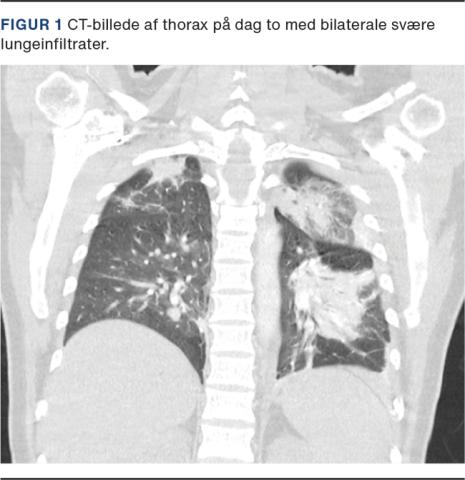

På indlæggelsestidspunktet havde hun en iltsaturation på 99% uden ilttilskud. Hun blev indlagt til observation, og man påbegyndte profylaktisk antikoagulansbehandling med tinzaparin 4.500 IE dagligt. Tilstanden forværredes hurtigt over det næste døgn med tiltagende dyspnø, faldende iltsaturation til 91% uden ilttilskud og blodtryksfald til 60/30 mmHg. Der blev iværksat intravenøs væskebehandling, og hun blev overflyttet til en intensivafdeling. Man udførte en akut CT med kontrast af thorax. Skanningen var uden tegn til lungeemboli, men afslørede svære bilaterale, pneumoniske infiltrater og konsolideret lungevæv (Figur 1). Der blev påbegyndt empirisk intravenøs behandling med cefuroxim mod evt. bakteriel superinfektion.